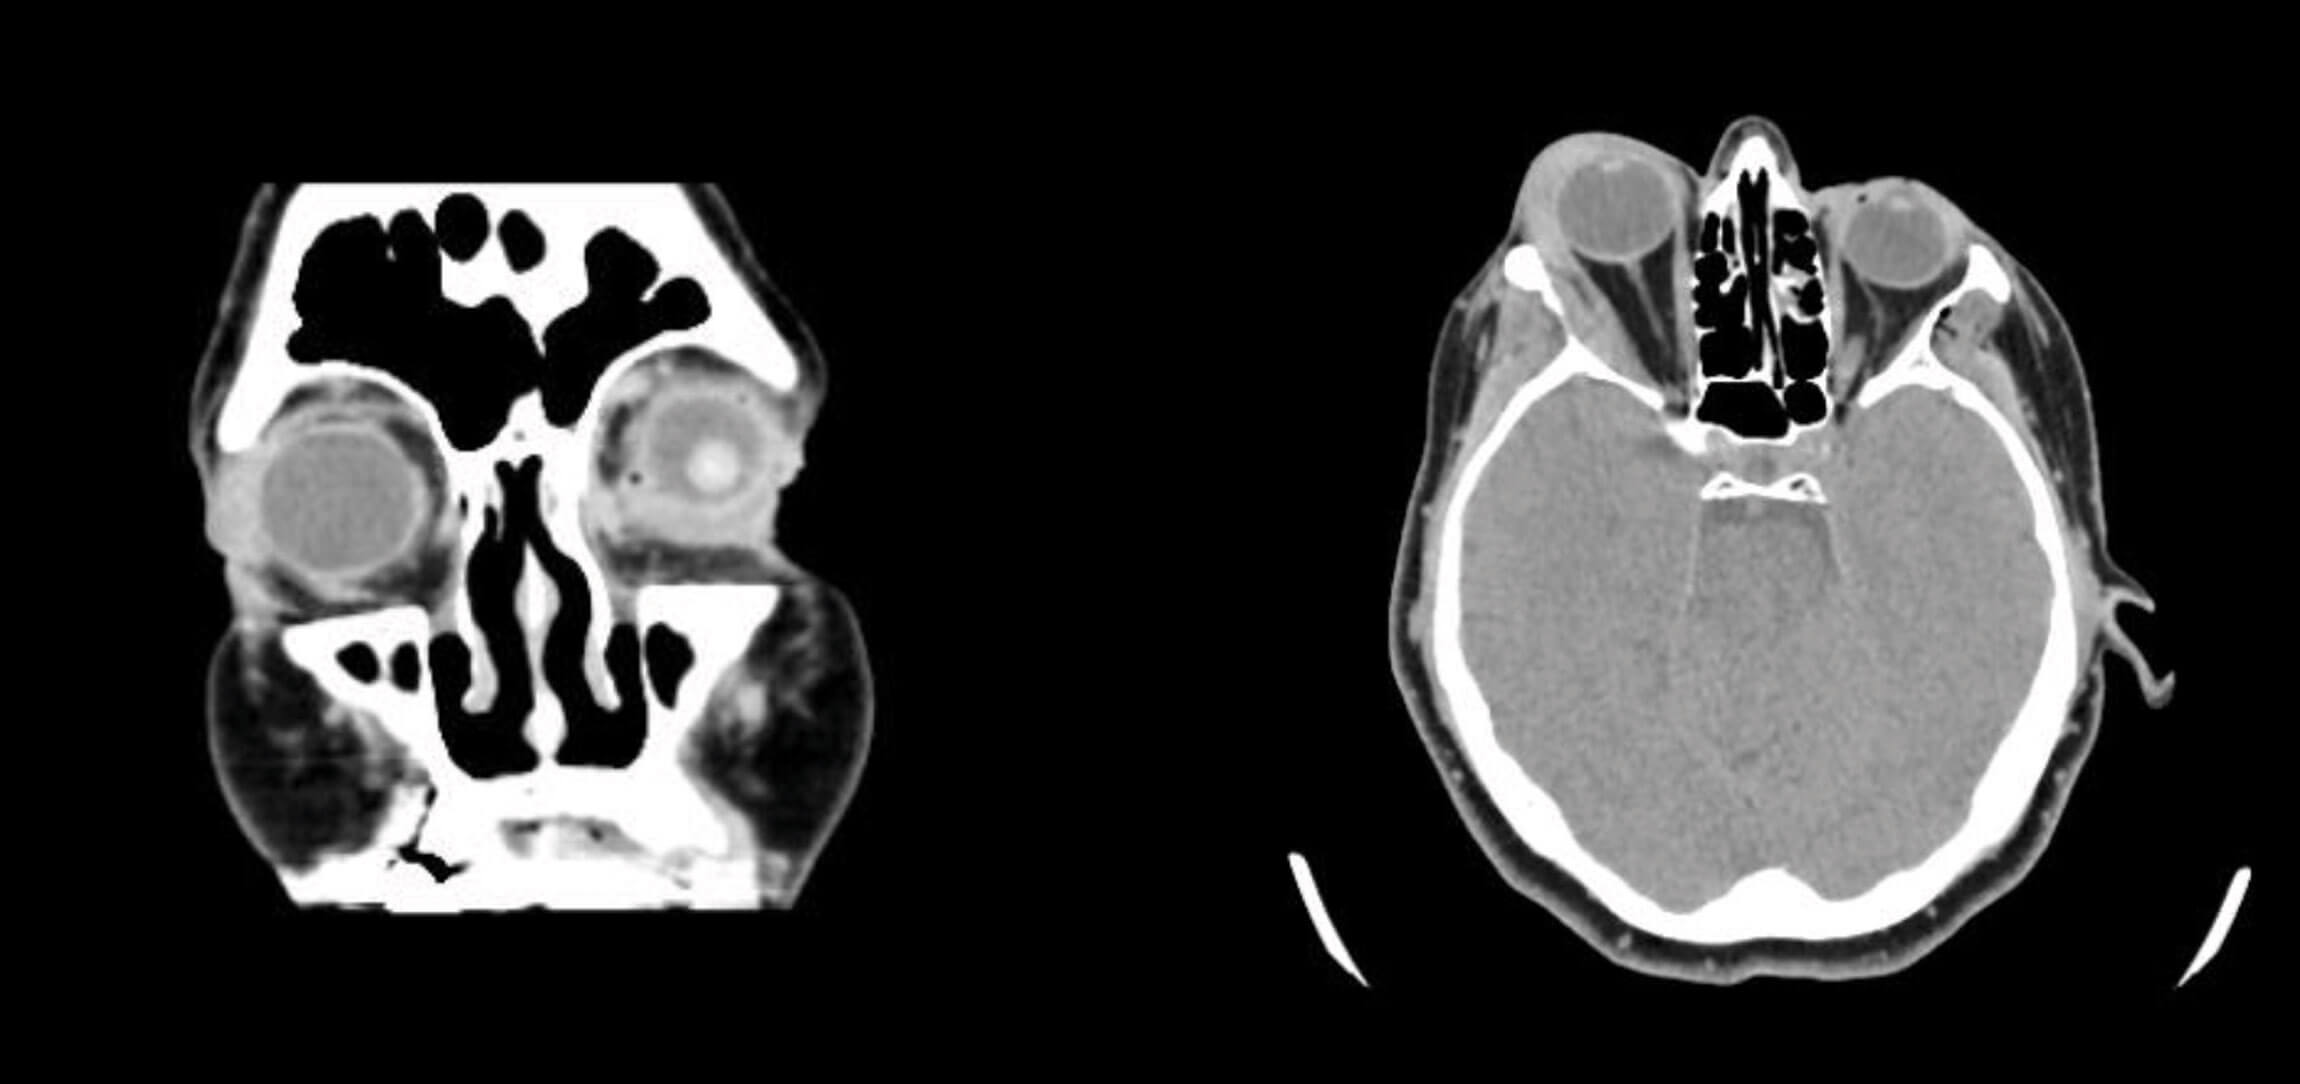

She was rushed to the emergency department where she arrived exactly 10 minutes following the injection. In the emergency room, a full ophthalmic examination was done. Her visual acuity was unremarkable with uncorrected 20/20 vision in the right eye, normal confrontational visual field, normal pupillary function, full unrestricted painless extraocular motility, and optic nerve function. A CT-scan of the brain and orbit was also undergone revealing an 8mm soft tissue thickening at the lacrimal fossa of the right orbit, lining its lateral border, medially displacing the lateral rectus muscle (Figures 3 and 4).

Figures 3 (left) and 4 (right): An 8mm soft tissue thickening at the lacrimal fossa of the right orbit involving the orbital and palpebral portions of the lacrimal gland. There is an additional linear thin soft density lining the lateral border of the right orbit adjacent to the right zygomatic bone, medially displacing the lateral rectus muscle.